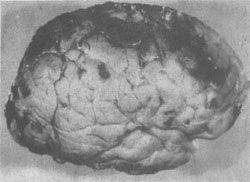

缺血性脑病的常见类型:①层状坏死。大脑皮质第3、5、6层神经元坏死、脱失、胶质化,引起皮质神经细胞层的中断。②海马硬化。海马锥体细胞损伤、脱失、胶质化。③边缘带梗死(图16-20)。梗死的范围与血压下降的程度和持续的时间有关,如血压持续下降,则梗死区自远心端向次远心端扩大,称为向心性发展(cardiopetal development),即C形梗死区向其两侧扩大,并自大脑顶部向颅底发展。大脑缺血性脑病边缘带梗死的极端情况是全大脑的梗死,但脑干的各核团由于对缺血(氧)的敏感性较低仍可存活。患者靠呼吸器以维持生命,但意识丧失,成为植物人。如何处置这样的病人则成为目前医学伦理学和医疗实践的难题。一旦这种病人死亡,其大脑乃成为由脑膜包裹,秽暗无结构的坏死组织,称为呼吸器脑。

图16-20 大脑缺血性脑病

大脑前、中、后动脉血供边缘带出血性梗死灶呈C形